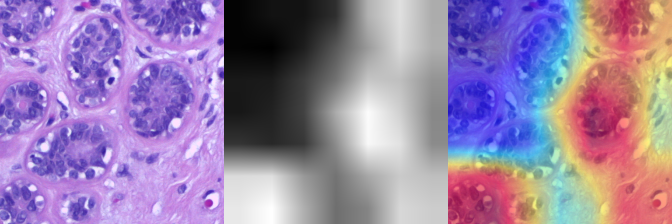

Explainable AI for Cancer Detection in Histopathology

GitHub Link